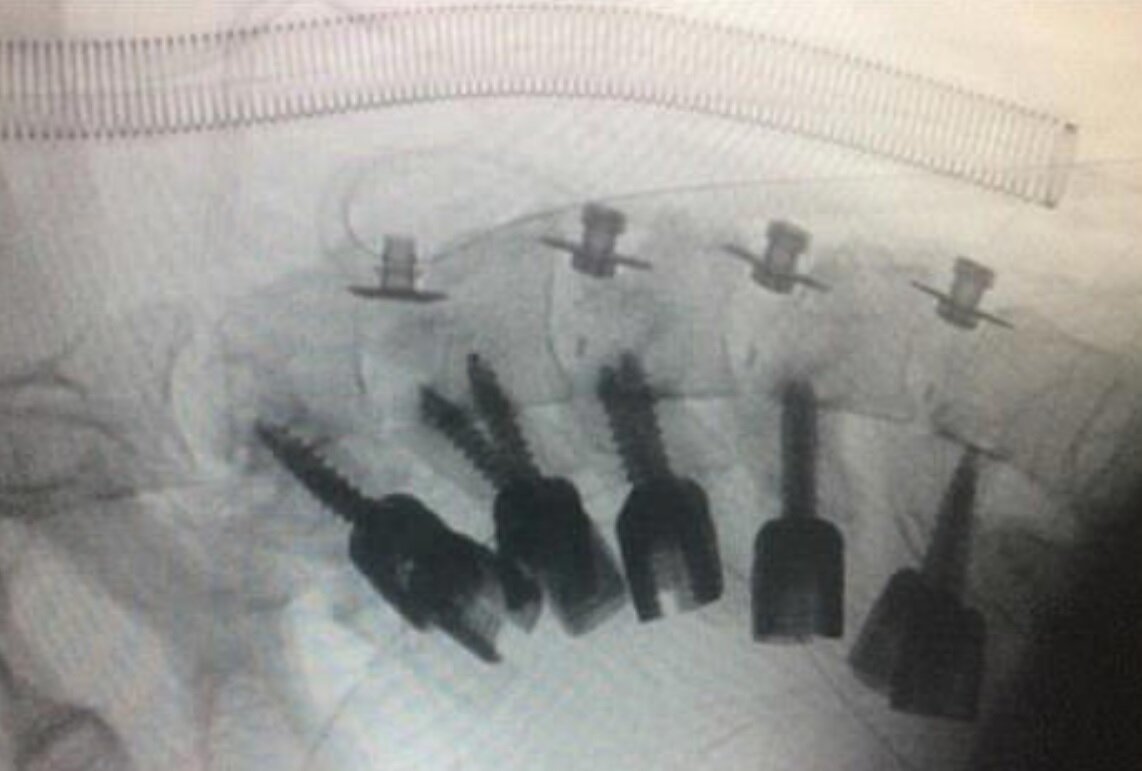

پزشکان گردن این جوان را جراحی کردند و با قرار دادن میله‌های فلزی در استخوان‌های گردن او، وضعیت گردنش را اصلاح کردند.